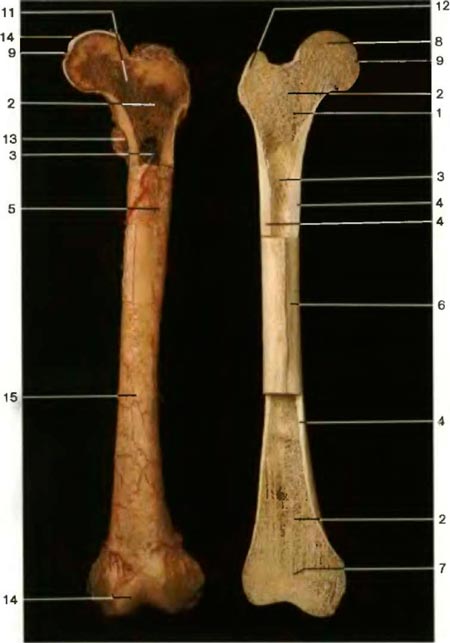

Бедренная кость взрослого человека. Бедренная кость взрослого человека. Слева: надкостница и кровеносные сосуды сохранены. Справа: венечный разрез проксимального и дистального эпифизов, показывающий губчатое вещество и костномозговую полость |

1. Метафиз

2. Губчатое вещество

3. Костномозговая полость

4. Компактное вещество

5. Питательный канал 6. Диафиз 7. Эпифизарная линия (остатки апифизарнои пластинки)

8. Эпифиз (головка бедренной кости)

9.Ямка головки бедренной кости

10. Перекладины губчатого вещества

11. Шейка бедренной кости

12. Большой вертел

13. Малый вертел

14. Суставная поверхность

15. Надкосгница

16. Кожа

1. Epiphysis

2. Substantia sponposa

3. Cavitas medulläres

4. Substantia compacta

5. Foramen nutricium

6. Diaphysis

7. Linea epiphysialis

8. Caput ossis femoris

9. Fovea capitis ossis femoris

10. Collum femoris

11. Collum ossis femoris

12. Trochanter maior

13. Trochanter minor

14. Facies atricularis

15. Periosteum